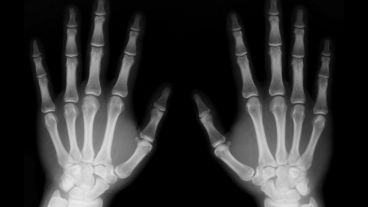

El viernes 7 de agosto, en el Auditorio del Cemar (San Luis 2020), se concretó un encuentro de capacitación orientado a trabajadores del área expuestos a radiaciones y al manejo de residuos peligrosos, a cargo de la Superintendencia de Riesgos del Trabajo de la Nación (SRT). Además, desde el organismo nacional inspeccionaron distintas dependencias del área de Salud y destacaron el avance en las gestiones del municipio para minimizar los efectos adversos que produce la utilización de Rayos X en profesionales y el medio ambiente.

Durante el encuentro, organizado en conjunto con la Municipalidad de Rosario, la Dirección de Diagnóstico por Imágenes de la Secretaría de Salud Pública, el Sindicato de Trabajadores Municipales y el Colegio Profesional de Técnicos Radiólogos, se remarcó que existen profesionales de diferentes especialidades de la salud que utilizan Rayos X sin conocer los efectos adversos de los mismos, por lo que es fundamental capacitar a los trabajadores para cuidar a los pacientes y a los propios empleados.

Cabe destacar que la Secretaría de Salud Pública está incorporando aparatos de diagnóstico por imágenes calibrados para ser utilizados con protocolos de radioprotección, tendientes a resguardar a pacientes, adultos y pediátricos y lograr de esta manera la mejor imagen con la menor radiación posible.